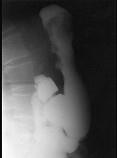

男,65岁,中上腹痛半年,X线检查如图,最可能的诊断是 ( )A.胃息肉B.胃溃疡C.胃浸润癌D.胃间质瘤E.糜烂性胃炎

问题 男,65岁,中上腹痛半年,X线检查如图,最可能的诊断是 ( )

选项 A.胃息肉 B.胃溃疡 C.胃浸润癌 D.胃间质瘤 E.糜烂性胃炎

答案 C